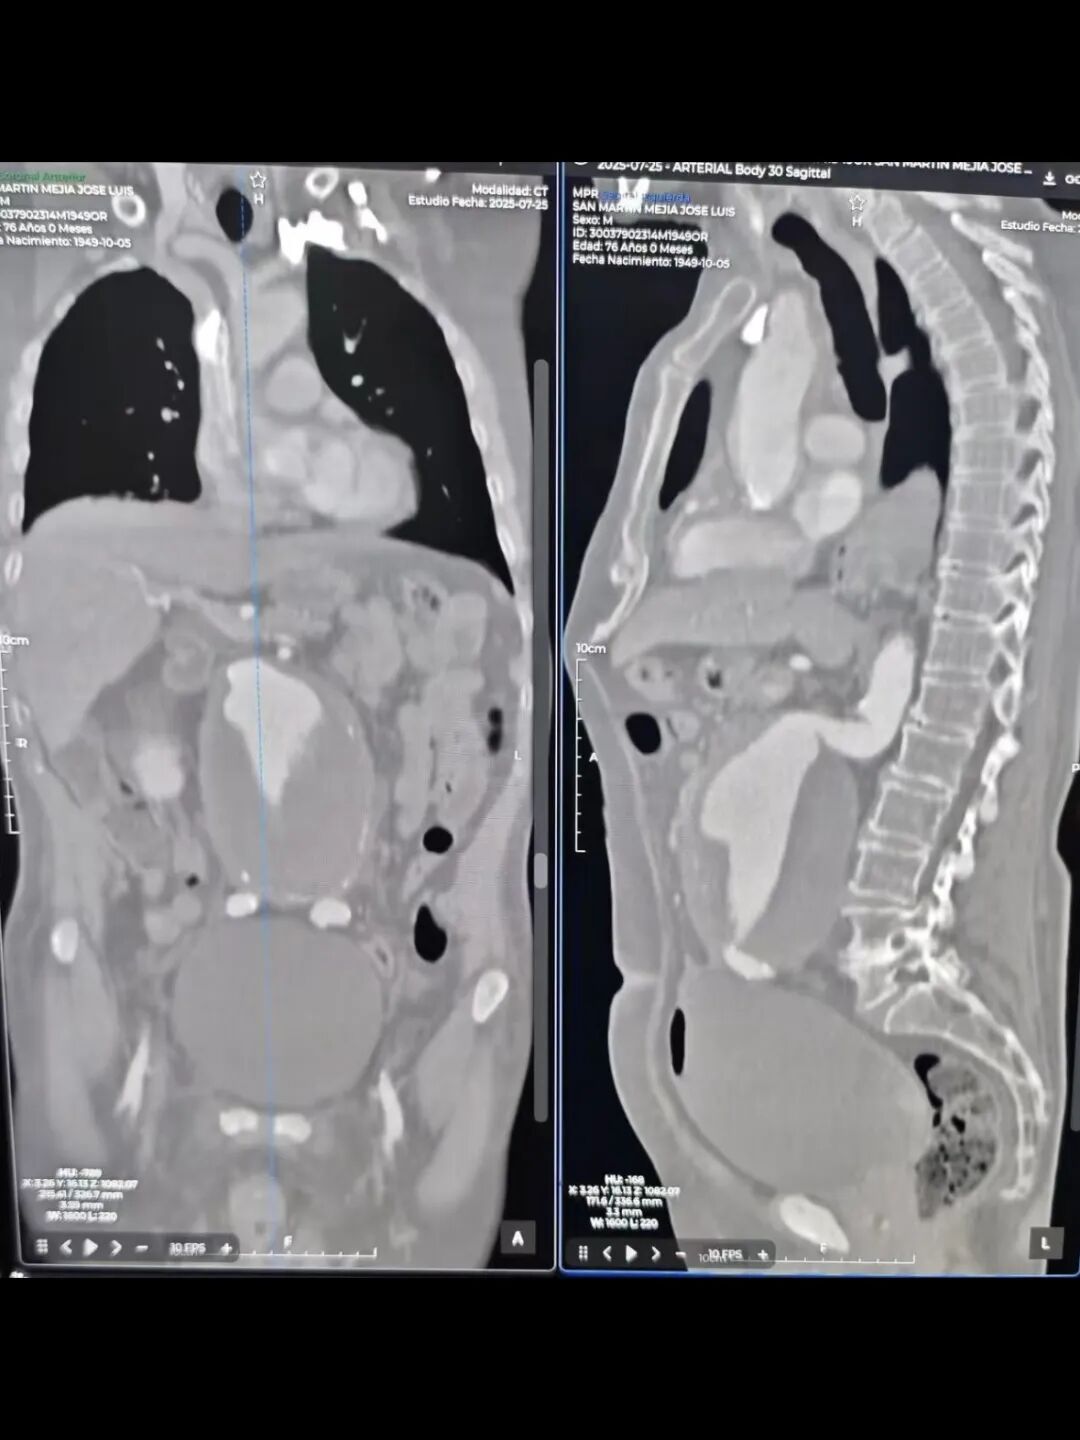

活动期间,在拜访墨西哥城拉腊兹国家医疗中心时,面对一例76岁男性高难度腹主动脉瘤患者,经诊断存在入路扭曲、短瘤颈且呈双重90度的复杂情况。若采用常规腹主动脉支架进行治疗,支架会难以通过病变区域,且难以贴合扭曲的近端健康锚定区,可能增加Type Ia内漏或支架移位等远期风险。当地医生团队在Nilo教授的指导下,根据术前影像及测量结果制定手术方案,选择使用 Aorfix?产品进行治疗。手术中结合Pushing Up技术和Socket旋转技术,成功应对复杂腔内环境并完成植入。术后造影结果显示,支架形态良好,腹主动脉血流通畅,无内漏,手术过程顺利,充分体现了 Aorfix?产品在应对高度扭曲、短瘤颈时出色的贴合性能,以及其Low Profile设计所带来的显著优势。

▲术前影像